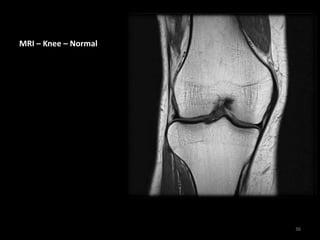

MRI – Knee – Normal

34

MRI for the Knee joint is

used to determine the

defects in meniscus,

cartilage , cruciate

ligaments and other

ligaments.

35